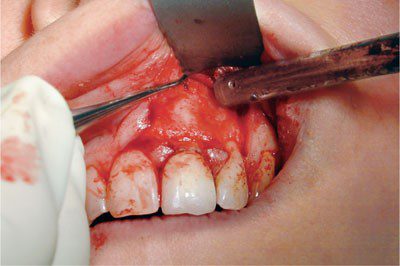

Lật vạt

Theo truyền thống, dụng cụ lật vạt dạng Howarth thường được sử dụng để lật vạt (hình 2-14).

Tuy nhiên, loại cây bóc tách này tương đối cùn. Việc sử dụng dụng cụ cùn hoặc sai hướng có thể gây tổn thương cho vạt và làm chậm quá trình lành thương sau đó. Chúng có thể khiến việc lật vạt khó khăn hơn và tốn thời gian hơn vì khó đưa vào mặt phẳng mô dưới màng xương.

Phẫu thuật nha chu hiện đại dựa vào cây bóc tách sắc bén để tách màng xương ra khỏi xương một cách hiệu quả. Ví dụ như cây bóc tách màng xương Buser, có một phần hình mũi giáo nhỏ để nâng gai nướu lên (hình 2-15) và cây bóc tách Hu-Friedy 24G, có phần sắc nét, cong để nâng phần vạt còn lại (hình 2-16) ).

Việc sử dụng dụng cụ bằng nhựa phẳng cũng có thể có giá trị trong việc lật gai nướu. Kích thước nhỏ của nó giúp giảm thiểu “chấn thương do nghiền nát” đối với các mô mỏng manh này.

Góc của các đường rạch ngang và dọc thường là nơi dễ dàng nhất để bắt đầu lật vạt vì độ căng của mô ở đây thấp. Nếu viền nướu đã được rạch kĩ thì chúng sẽ dễ dàng được lật ra khỏi xương. Khi gặp khó khăn trong việc lật gai nướu thì nên rạch lại đường rạch trong khe nướu ban đầu lần thứ ba nếu cần thiết.